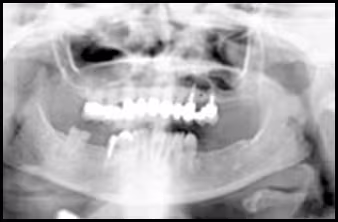

These figures demonstrate the effects of head tilting on the resultant image.

Figure 44A. Panoramic Image.

Figure 44B. Panoramic Schematic.